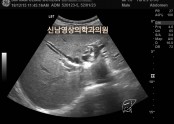

• 소리 없이 찾아오는 침묵의 암이라 불리는 담도암, 담관암

• 담도암은 국내 10대 암에 속하는 암입니다.당남과 담도암 발생 건수에서 남녀를 합친 연령대별로 살펴보면 70대가 36.3%로 가장 많았고, 60대가 24.7% 80대 이상이 24.1% 순으로 결과적으로 나이가 들면서 발생하는 암입니다.담도암이 발생하는 명확한 원인은 참…